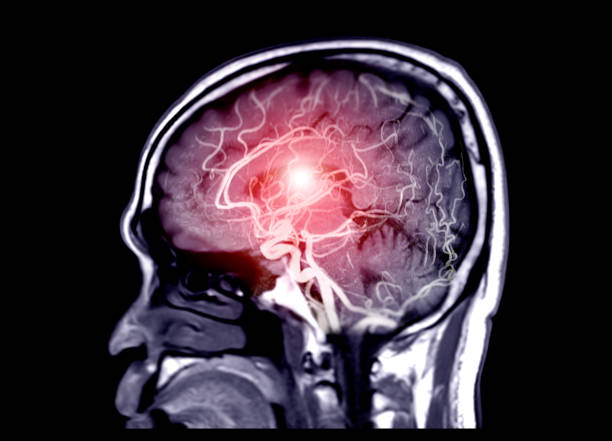

뇌졸중 증상

모야모야병의 가장 일반적인 증상 중 하나입니다. 뇌졸중 증상은 언어 장애, 인지 장애(기억력 감퇴, 학습 장애 등), 시각 장애(시야 손실, 양안 시력 장애), 운동 장애(양쪽 다리나 팔의 약화, 불균형, 혹은 어색한 움직임 등) 등이 있습니다.

반복성 뇌졸중

모야모야병은 뇌졸중 발생 위험이 높습니다. 반복적인 뇌졸중은 뇌조직 손상, 체력 저하, 기능 손상 등을 초래할 수 있습니다.